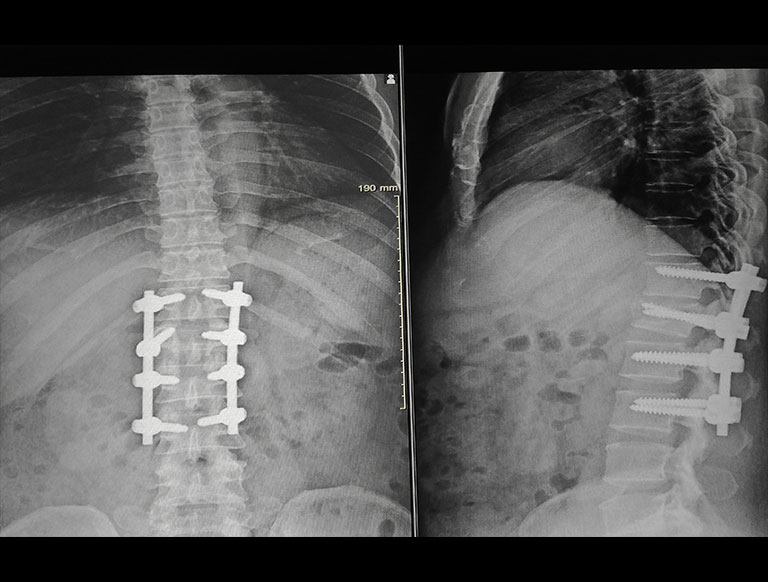

Instrumented Spinal Fusion Asian Spine Hospital New delhi: asian spine hospital, india’s first centre of excellence and training institute for full endoscopic spine surgery, has registered a momentous achievement with the successful completion of 200 spinal fusion surgeries (endofusion) using keyhole endoscopic spine technology. Asian spine hospital, india’s first centre of excellence and training institute for full endoscopic spine surgery, proudly announces a momentous achievement with the successful completion of 200 spinal fusion surgeries (endofusion) using keyhole endoscopic spine technology. Asian spine hospital, a full endoscopic spine surgery centre, announced a significant achievement with the successful completion of 200 spinal fusion surgeries (endofusion) using keyhole endoscopic spine technology, the hospital informed in a press statement on monday. Our surgical approach address life altering pain, spinal conditions and disorders, including bone spurs, cervical spondylosis, cranio vertebral junction anomalies, degenerative disc disease, etc. The instruments are inserted through very small access ports (<1cm) to reach the spinal column; all the manipulations with the instruments can be directly controlled through these ports. The hospital’s commitment to clinical excellence, coupled with ground breaking achievements like the completion of 200 full endoscopic spinal fusion surgeries (endofusion) solidifies its position as a beacon of innovative spinal healthcare in the world.

Minimally Invasive Spinal Fusion Asian Spine Hospital Asian spine hospital, a full endoscopic spine surgery centre, announced a significant achievement with the successful completion of 200 spinal fusion surgeries (endofusion) using keyhole endoscopic spine technology, the hospital informed in a press statement on monday. Our surgical approach address life altering pain, spinal conditions and disorders, including bone spurs, cervical spondylosis, cranio vertebral junction anomalies, degenerative disc disease, etc. The instruments are inserted through very small access ports (<1cm) to reach the spinal column; all the manipulations with the instruments can be directly controlled through these ports. The hospital’s commitment to clinical excellence, coupled with ground breaking achievements like the completion of 200 full endoscopic spinal fusion surgeries (endofusion) solidifies its position as a beacon of innovative spinal healthcare in the world.